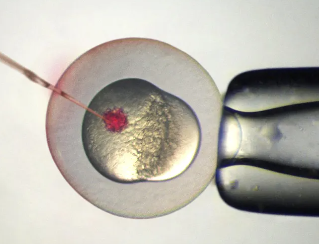

石家庄试管三代成功率高吗,成功率医院排名公布(图1)